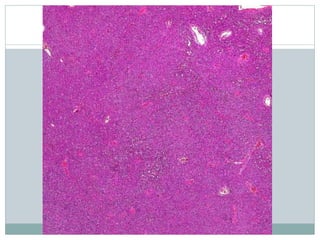

Architecture  Sheets (denselypacked)  Homer-Wright rosettes in PNET  Minimal intercellular collagen or reticulin  Rare myxoid change with microcyst formation  Necrosis with perivascular preservation of cells

• #11 Ewing sarcoma (ES) is a highly cellular, high-grade sarcoma with a dense, solid to sheet-like distribution of cells, as depicted. Most tumors are diagnosed on small biopsy prior to treatment with chemotherapy, and large, preserved sections, as shown, are uncommon.

• #15 Coagulative necrosis is common in ES and is often geographic in distribution. A common finding is the presence of perivascular tumor cell preservation ("peritheliomatous growth") with degeneration and death of surrounding cells.